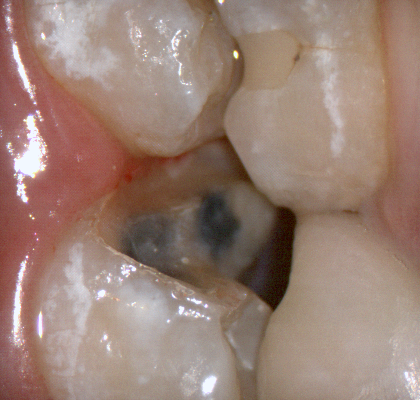

The following pictures depict the sequence of burs we recommend that you use to finish a preparation quickly. While patient is getting numb, take a quick look at the clearance you will need to reach proper material thickness. Once the quadrant is isolated with isolite and optragate, take an occlusal router bur and create a trough to gain the proper depth. Follow that with a flat disk, and you can quickly reduce the occlusal height.

A shoulder bur of .8 mm thickness can help you reduce the interproximal areas as well as the buccal and lingual margin lines. Before finishing the prep, place hemostatic agent like expasyl in the sulcus and place retraction cord. while it is setting, check your reduction. If you need more space, now is the time to reduce some more.

Once you have adequate clearance, retraction, and hemostatis, you can readily image and find your margins in the CAD software